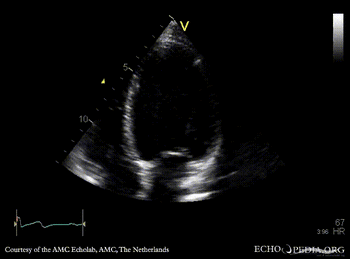

Dilated cardiomyopathy

A4CH: Color Doppler, moderate mitral regurgitation